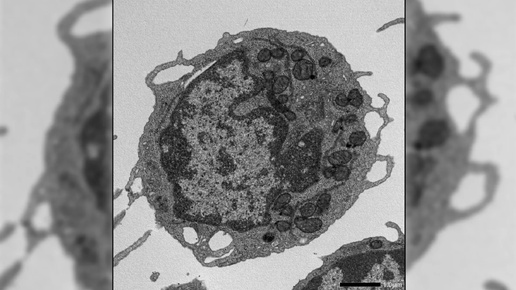

Группа ученых из Японии и США обнаружила неожиданного виновника этого процесса. Оказалось, что белок MLKL, известный как триггер клеточной смерти, ведет скрытую двойную игру 🧬. Под воздействием возрастного стресса он не убивает клетки, а проникает в их энергетические станции — митохондрии — и буквально выводит их из строя. Это лишает кровь способности обновляться, а наш иммунитет — надежной защиты. Исследователи...